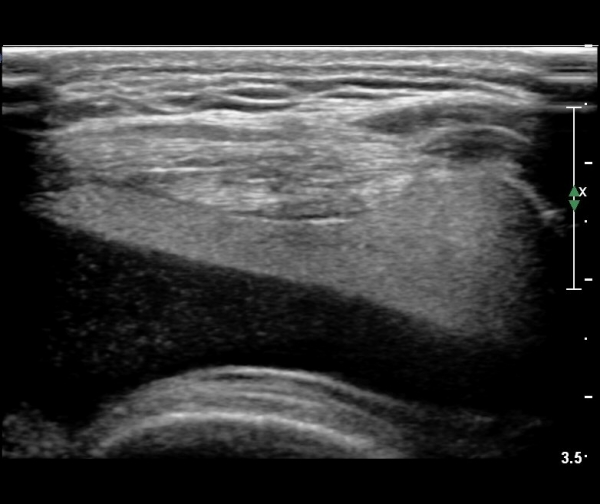

¹«¸­ Àü¸éºÎ Á¾´Ü¸é°Ë»ç¿¡¼­ °üÀý³» ¼ö¾×Àú·ù°¡ °üÂûµÇ´Âµ¥ ¼ö¾×Àú·ù Ç¥Ãþ¿¡ °í¿¡ÄÚ Áö¹æÃþÀÌ °üÂûµÊ(»çÁø 2, 3)

¹«¸­ Àü¸éºÎ Ⱦ´Ü¸é°Ë»ç¿¡¼­ °üÀý³» ¼ö¾×Àú·ù°¡ °üÂûµÇ´Âµ¥ ¼ö¾×Àú·ù Ç¥Ãþ¿¡ °í¿¡ÄÚ Áö¹æÃþÀÌ °üÂûµÊ(»çÁø 4, 5)